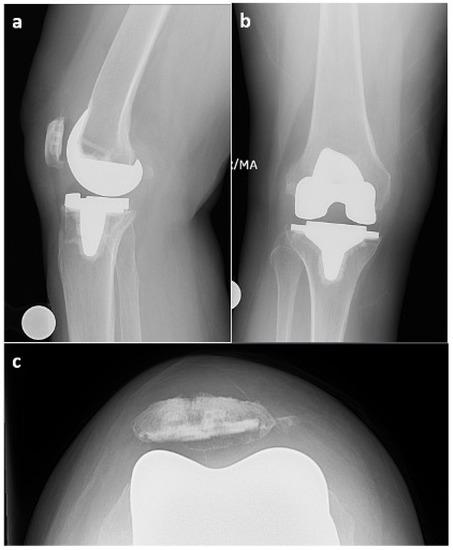

An MRI of the right knee was also performed and demonstrated pronounced debris-containing synovitis with the appearance of diffuse rice bodies in the anterior compartment and medial and lateral gutters (Figure 3). Distinguishing SC from rice bodies in the context of a PJI can be challenging. Rice bodies and SC both involve the formation of loose bodies, yet their origin and associated conditions vary. Additionally, the MRI appearances can be similar, making it hard to distinguish between the two. Both conditions can appear as multiple bodies within the joint space, with signal characteristics that can overlap. On the MRI, PJIs present as effusion and potentially synovial thickening, which might also complicate the distinction between rice bodies and synovial chondromatosis. In such complex scenarios, a histopathological examination is often necessary to confirm the diagnosis. The radiology report in this case stated that the presence of rice bodies (rice bodies are described as iso- and hypointense to skeletal muscle tissue, whereas SC would appear slightly hyperintense [10]) was compatible with the clinical concern of infection. However, the ability to rule out PJI was complicated by the patient’s elevated ESR and CRP and the diagnosis of anti-phospholipid syndrome with positive rhetological markers (ANA+).

Figure 3. MRI of right knee 3 October 2022 (GE, Coil: HD TRknee PA): (a)—sagittal plane (proton density—PD), (b)—axial plane (PD). Dotted red line outlines the appearance of diffuse rice bodies in the anterior compartment and medial and lateral gutters.